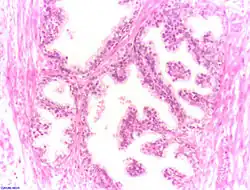

Der Querschnitt der Prostata kann in drei Zonen unterteilt werden, die sich in den Ausführungsgängen der Drüsen unterscheiden: die periurethrale Mantelzone, die Innenzone und die Außenzone. Die Ausführungsgänge der Drüsen in der inneren Zone enden direkt in die Harnröhre. Die Drüsen in der äußeren Zone sammeln ihr Sekret in gemeinsamen Ausführungsgängen, bevor sie in der Harnröhre enden. Diese Einteilung ist bei der Entstehung von Tumoren von Bedeutung (s. unten).

Die Ausführungsgänge (Ductuli prostatici) der Prostatadrüsen in der Prostata münden im Sinus prostaticus beidseits des Colliculus seminalis (Samenhügel) der Harnröhre. Ihr Drüsenepithel ist funktionsabhängig entweder einschichtiges Plattenepithel oder mehrreihiges hochprismatisches Epithel. Der Hohlraum (Lumen) der Drüsen enthält Concretio prostatica, konzentriertes geschichtetes Sekret.

Das Drüsenepithel setzt sich aus drei Zelltypen zusammen: am häufigsten sind basale und luminale sekretorische Zellen, die unterschiedliche Keratin-Subtypen exprimieren und sich dadurch unterscheiden lassen. Luminale Zellen zeichnen sich zudem durch die Expression von prostataspezifischem Antigen und Androgenrezeptor aus. Sehr viel seltener kommen als dritter Typ neuroendokrine Zellen vor, die anhand der von ihnen produzierten Neuronenspezifischen Enolase und verschiedener Neuropeptide identifiziert werden können. Stammzellen in der basalen Zellschicht bilden vermutlich die Vorläufer aller dieser Zelltypen.

Zwischen den Drüsen liegen glatte Muskelzellen, die sich bei der Ejakulation zusammenziehen und so das Sekret ausstoßen, und Bindegewebe mit elastischen Fasern, das sogenannte Stroma myelasticum prostatae.